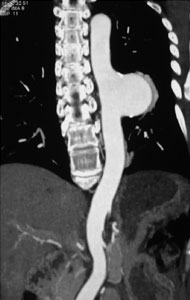

症例1

59歳 女性

腹痛・体重減少(10kg)

平成15年7月より毎食後に腹痛出現。

平成18年5月他院腹部血管造影にて腹部動脈閉塞を認めたが、加療されず。

7月当院受診。

高血圧(+) 糖尿病(−) 喫煙歴(−)

【治療計画】

SMA PTA/stent(Brachial approach)

腹部血管造影検査